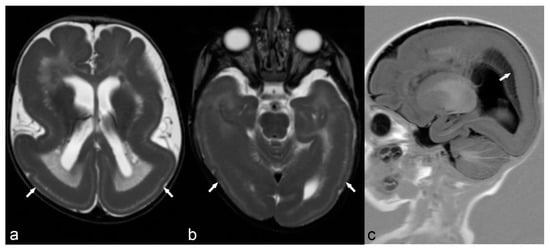

Auto-immune encephalitis is a less frequent cause of epilepsy characterized by high T2/FLAIR signal of the temporal lobe (including the hippocampus), insula and cingulum, usually with bilateral symmetrical or asymmetrical involvement (Figure 13).

Figure 13.

50-year-old woman. Symmetrical hyperintensity is identified on coronal T2WI (a) and FLAIR (b) in both hippocampi (arrows). No abnormal enhancement is seen on 3D T1 Gd (c). This is a case of autoimmune limbic encephalitis.